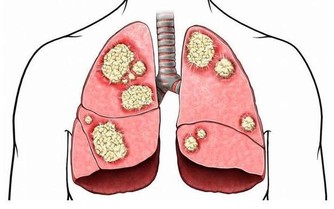

喝水多沒有尿意,一般認為是少尿或者是無尿的情況。無論是哪一種情況,都和是否喝水,喝水多少並沒有關係,主要是看尿液總量。每天的尿液總量,不到400毫升屬於少尿,不到100毫升屬於無尿。這些情況的出現,和飲水量以及出汗量有關係,飲水少、出汗多的人往往會出現少量的情況,在一些熱衷於運動的人身上比較常見。除去這種生理性因素之外,一樣可能是身體方面的問題。當它的過濾能力逐漸下降時,尿液的形成過程也就出現了問題,尿液量會顯著減少,同樣是不容忽視的。